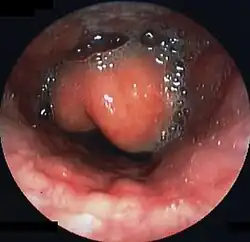

Diagnosis may be confirmed by direct inspection using a laryngoscope, although this may provoke airway spasm.[15] If epiglottitis is suspected, diagnosis is made on basis of fiberoptic laryngoscopy exam carried out in controlled environment like an operating room.[16][17]

Swollen epiglottis in laryngoscopy